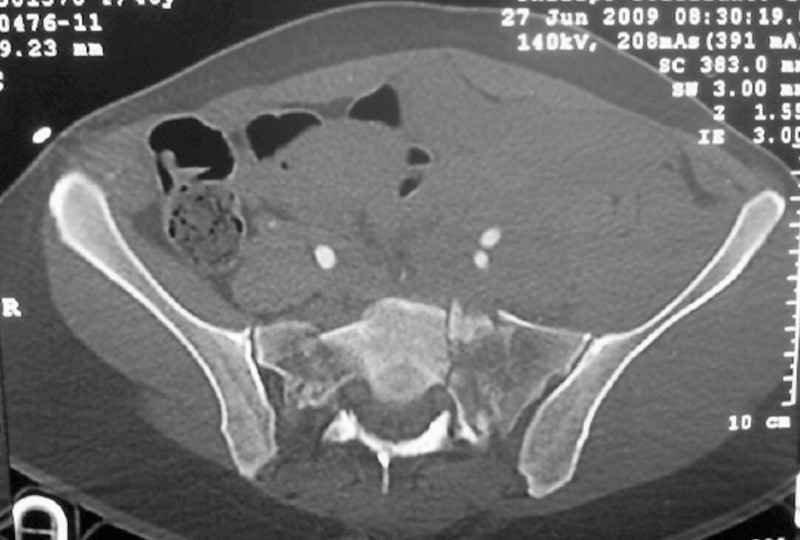

This patient has extensive and complicated skeletal injuries...much more data (such as additional relevant images and clinical information regarding the soft tissues and overall patient status) would help us formulate an informed plan.

The sacral pattern alone is quite difficult and seems to be some version of an H-pattern, but I can’t tell from these films.

The soft tissues are also in mild condition, buttock hematoma and probably a Morel-Lavalle. I send some more CT images. There are some conminution in the posterior column (I don’t have images now). The patient is scheduled for surgery next Monday. The plan is percutaneous sacral fixation and then ilioinguinal approach .

I am a huge fan of closed reduction and percutaneous posterior pelvic fixation, but that particular sacral injury warrants an open reduction.

I’d begin with that in order to have a high quality osseus foundation for subsequent acetabular repair.